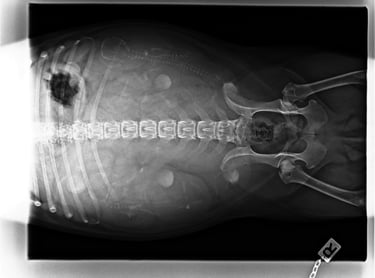

24.09.2025

58ter Trächtigkeitstag.....

Heute wurde unsere Hedi geröntgt, ihr geht es noch gut, der Countdown läuft: In zwei, drei Tagen lüftet unsere Hedi ihr Geheimnis.... Vom Röntgenbild haben wir uns mehr versprochen, aber na gut vier Welpen sind auf jeden Fall gesichtet worden..... Und wir freuen uns und sind sehr gespannt was Letzt endlich kommen wird :-))

Gewicht: 12 kg